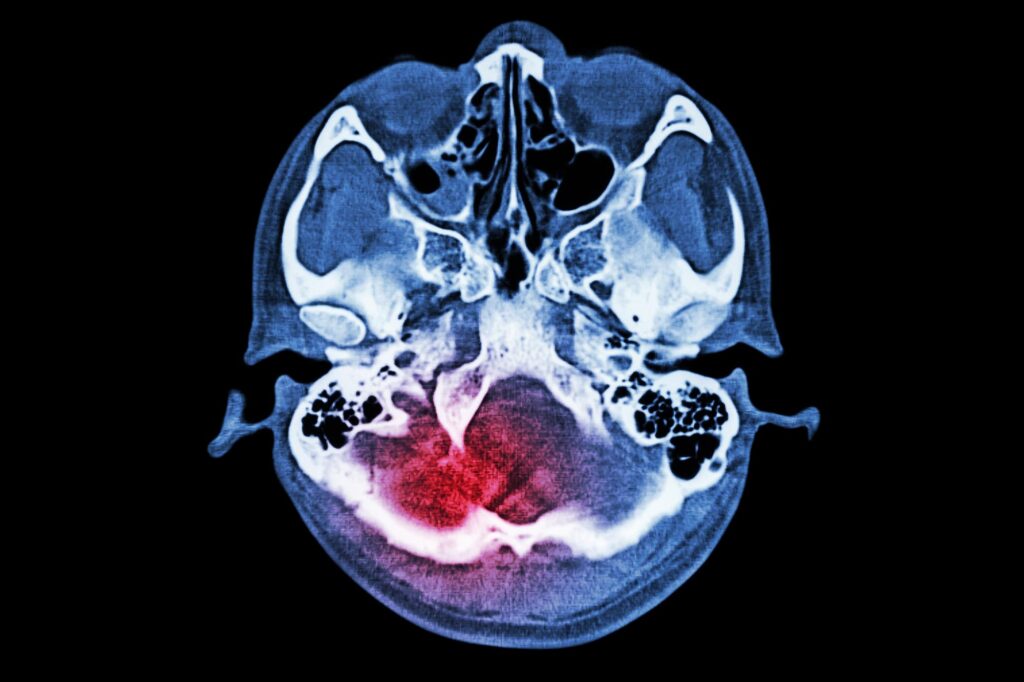

חוקרים מאוניברסיטת טורונטו גילו וירוס RNA חדש, Apocryptovirus odysseus, המחמיר את הטוקסופלזמה בשילוב עם הטפיל Toxoplasma gondii, ומציע תובנות לגבי אסטרטגיות טיפול פוטנציאליות חדשות לזיהומים טפיליים. חוקרים גילו Apocryptovirus odysseusוירוס RNA חדש הקשור לדלקת חמורה בבני אדם הנגועים בטוקסופלזמה גונדי. צוות בינלאומי בראשות חוקרים מאוניברסיטת טורונטו מצא חדש RNA נגיף ...